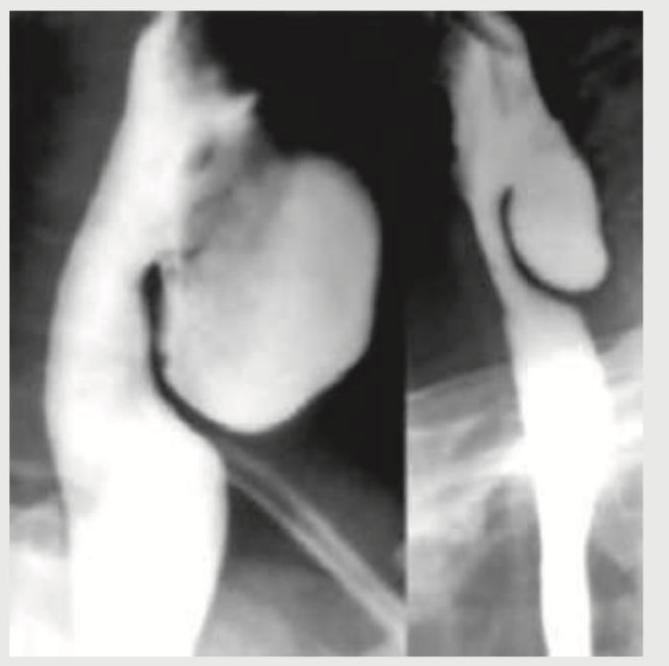

A 58-year-old male patient presents with halitosis, mild dysphagia and regurgitation of previous day food. Barium study is performed. Where is the location of this presentation?

Explanation: ***Posterior segment of the esophagus along inferior pharyngeal constrictor muscle*** - The symptoms of **halitosis**, **dysphagia**, and **regurgitation of undigested food** are classic for a **Zenker's diverticulum**, which is a **pharyngoesophageal pouch**. - This diverticulum forms due to herniation of the pharyngeal mucosa through a weak point (Killian's triangle) in the **posterior pharyngeal wall**, specifically above the cricopharyngeus muscle (part of the **inferior pharyngeal constrictor**). *Anterior segment of the esophagus along superior pharyngeal constrictor muscle* - **Zenker's diverticulum** is located posteriorly, not anteriorly. - It arises in relation to the **inferior pharyngeal constrictor muscle**, not the superior pharyngeal constrictor. *Posterior segment of the esophagus along superior pharyngeal constrictor muscle* - While Zenker's diverticulum is **posterior**, it is associated with the **inferior pharyngeal constrictor muscle** (specifically the cricopharyngeus muscle in Killian's triangle), not the superior pharyngeal constrictor. - Herniation occurs above the **cricopharyngeus muscle**, which is the lowermost part of the inferior pharyngeal constrictor. *Anterior segment of the esophagus along inferior pharyngeal constrictor muscle* - **Zenker's diverticulum** is a **posterior** herniation, not an anterior one. - Although it involves the **inferior pharyngeal constrictor muscle**, its posterior location is a defining characteristic.